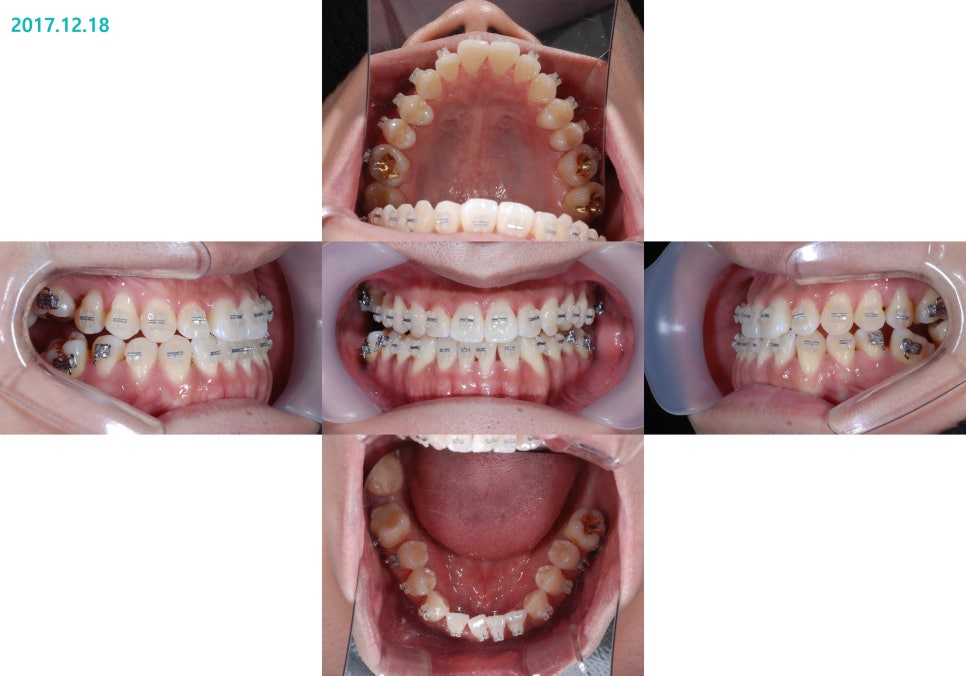

½ÉÇÑ ¹Ý´ë±³ÇÕÀÌ

¾Õ´Ï³¢¸® ¸Â´ê´Â Á¤µµ±îÁö

°³¼±µÈ °ÍÀ» º¼ ¼ö ÀÖ½À´Ï´Ù.

½ÉÇÑ ÁÖ°ÆÅÎÀÌ °³¼±µÇ¸é¼­

À§¾Æ·¡ ¾Õ´Ï°¡

Á¤»óÀûÀ¸·Î ±³ÇÕµÇ°Ô ¹Ù²ï °ÍÀ»

º¼ ¼ö ÀÖ½À´Ï´Ù¸¸

¾ÆÁ÷Àº ±³ÇÕÀÌ ºÒ¾ÈÀüÇÑ »óÅÂÀÔ´Ï´Ù.

¿À¸¥ÂÊ ¾î±Ý´Ï°¡ À¯Âø(Ankylosis)ÀÌ ÀÖ¾î

¿òÁ÷ÀÌÁö ¸øÇÏ´Â °ÍÀÌ È®ÀεǾú½À´Ï´Ù.